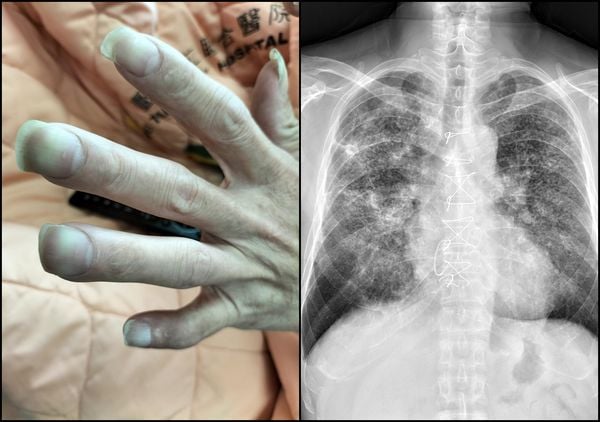

十指变杵状指确诊肺结核 医生:一旦发现速就医

(苏一峰脸书照片)

(台北25日综合电)许多人体内发生问题时,身体外观可能会出现明显变化。台湾胸腔内科医生苏一峰表示,他近日替一名40岁男性病患治疗时,发现对方的十只手指全部都出现“”,马上替男子照了X光,只见“满天星的肺结节”。

他指出,这名男子完全不,最近喘了好几个月,才决定到医院治疗,他一看就发现,手指是明显的杵状指,且几乎十根手指都如此,再照X光就看到满天星的肺结节,成千上万颗肺结节,让密集恐惧症的人头皮发麻。

(中国附医照片)

台卫福部国健署曾表示,杵状指是肢端末梢肥大的现象,常造成指甲床跟指节的角度变形,可能会出现于有“心肺”相关疾病造成身体缺氧或有消化系统疾病的患者身上,但并非所有的肺癌患者都会出现杵状指。

皮肤科医师黄景昱曾指出,许多肺部疾病都会引发杵状指情况,例如肺癌、、肺脓疡、慢性阻塞性肺病等,这些肿瘤会释放激素、生长因子,刺激肢体末梢组织增生,因此手指头会变得异常肥大;心脏疾病也会导致类似状况,包括法洛氏症候群、开放性动脉导管、心内膜炎等。(ETtoday新闻云)